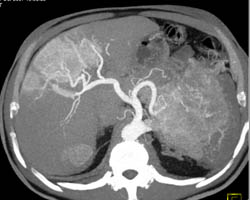

Islet Cell Tumor With Liver Metastases